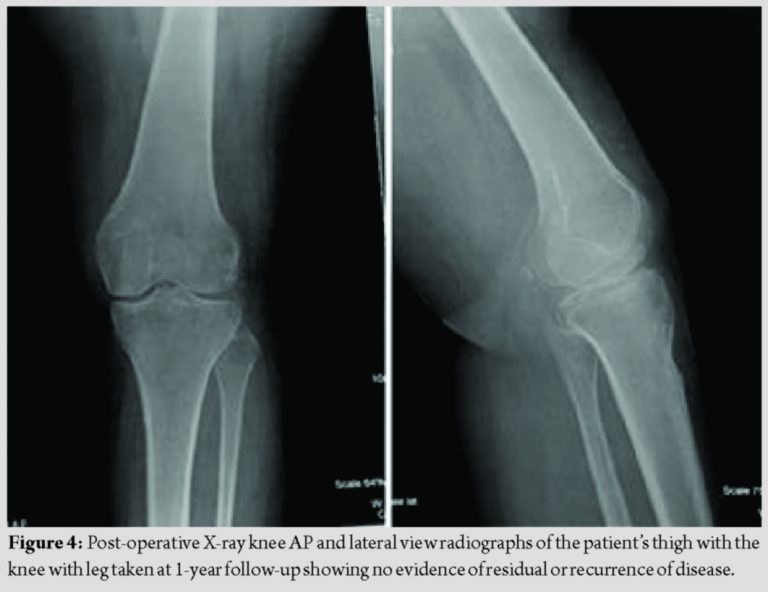

Postoperatively, the patient received three cycles of chemotherapy as per protocol. At 1-year follow-up, the patient was able to perform activities of daily living without any discomfort. The range of motion was 0–90° degrees. The patient is still under regular follow-up with no evidence of recurrence. She could ambulate unaided with no extensor lag.